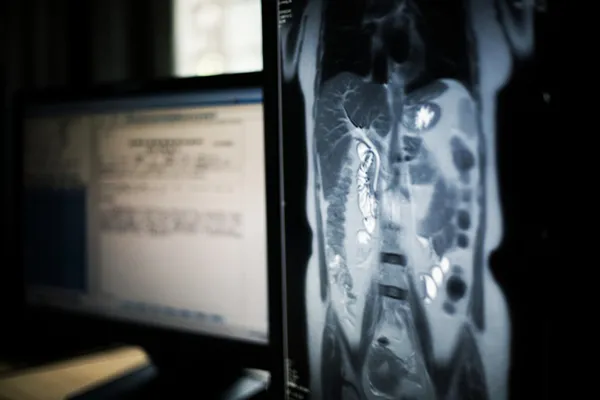

Dr. Öğr. Üyesi İlhami Gültepe, karaciğer yağlanmasının nasıl teşhis edildiği hakkında ise şu bilgileri paylaştı:

"Muayene sırasında büyümüş karaciğer doktorun eline gelebilir. Karaciğer enzimlerindeki artış karaciğerdeki inflamasyonun bir belirtisidir. Ultrasonla yağlanmanın derecesi tespit edilebilir ama hekim gerekli gördüğünde karaciğer biyopsisi de isteyebilir. Biyopsi, yağlanmanın şiddetini tespit etmeye yarayan en iyi yöntemdir."